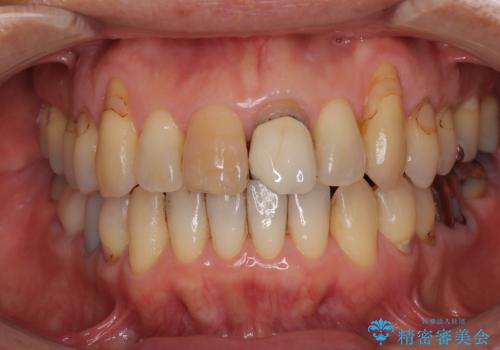

- 幼少期にぶつけてしまった前歯2本の変色を気にして来院された患者様です。

神経は生きているものの歯の色が茶色くなってきており、隣の歯は保険診療で装着したプラスチックのクラウンが徐々に黄ばんできている状態でした。

2本を同時にオールセラミッククラウンにて補綴治療を行うこととしました。